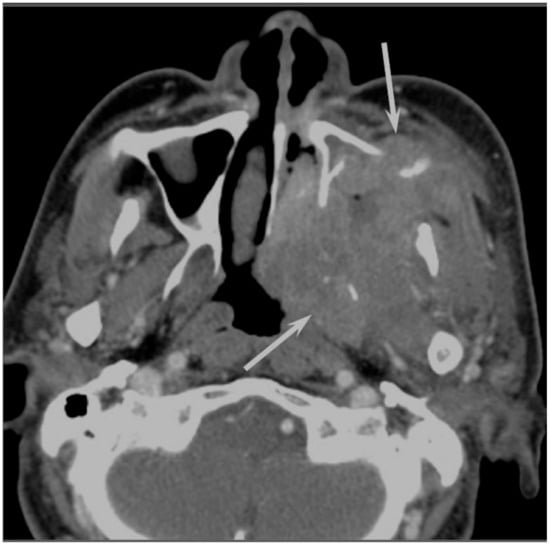

On CT, sinonasal lymphomas frequently show both infiltrative or permeative bony invasion and exhibit varying degrees of regional bony destruction [12]. NHLs with permeative-type tumor invasion typically cross the sinus wall and exhibit remnants of sinus wall as a linear structure within the tumor (Figure 5) [24]. In contrast, bony resorption or remodeling caused by the lymphoma may also be accompanied by bone sclerosis [25]. NHLs usually show isointensity on T1WI and slightly hyperintensity on T2WI [11]. Although the signal intensity of NHLs is nonspecific, the ADC measurement helps differentiate these tumors from other malignancies. In the maxillary sinus, the ADC values of NHL (0.61 × 10−3 mm2/s) were shown to be lower than those of SCCs (0.95 × 10−3 mm2/s), which reflects the greater cellularity of NHLs [12]. Although NHLs usually appear as a homogeneously enhanced mass, necrotic areas within the tumor are occasionally observed in NK/T-cell lymphoma [26,27].

Figure 5. Diffuse large B-cell lymphoma of the left maxillary sinus. Contrast-enhanced CT image showing a homogeneously enhanced lesion accompanied by remaining sinus walls as a linear structure within the tumor (arrows).